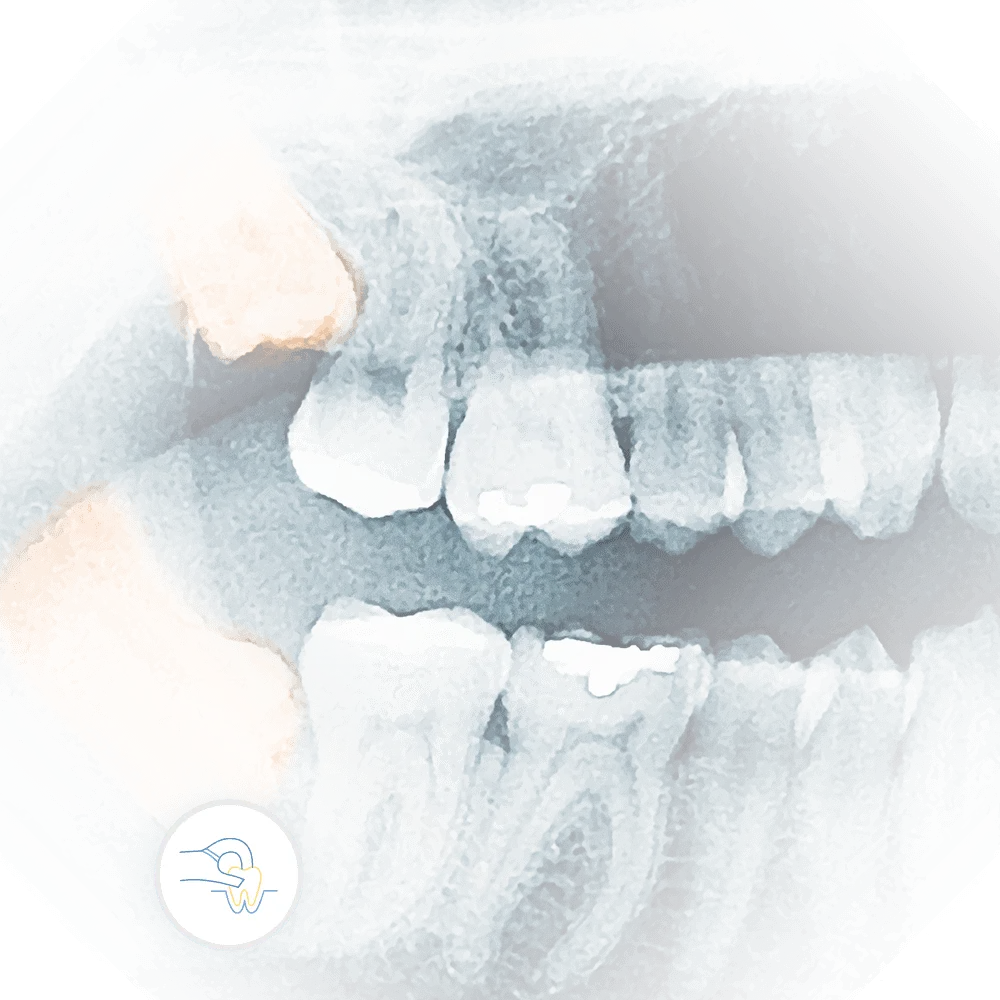

x-ray of impacted teeth requiring dental tooth extraction

Tooth Extractions

Left untreated, gum disease can escalate to severe health problems. At Vartanian Dental Group, our specialized team focuses on early diagnosis and effective treatment to restore your gum health and prevent further issues.